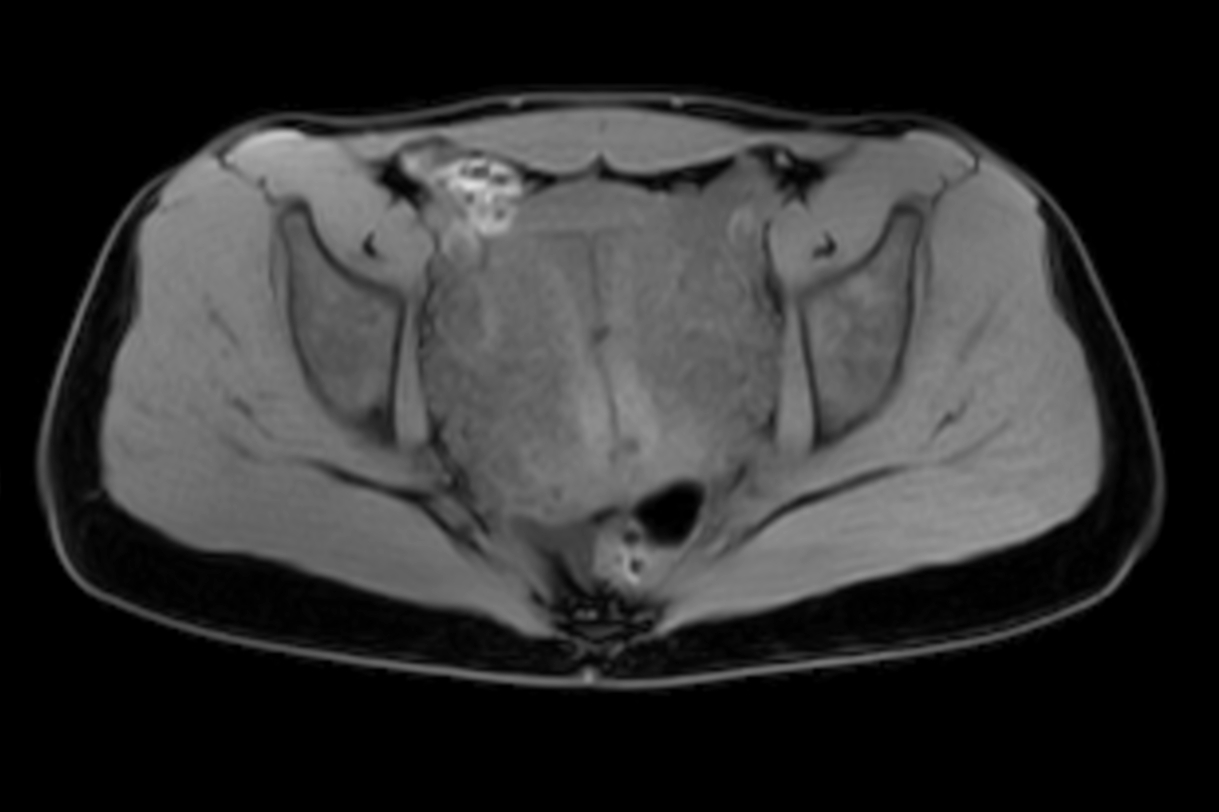

Axial mDIXON XD - T1w FFE (Water only)